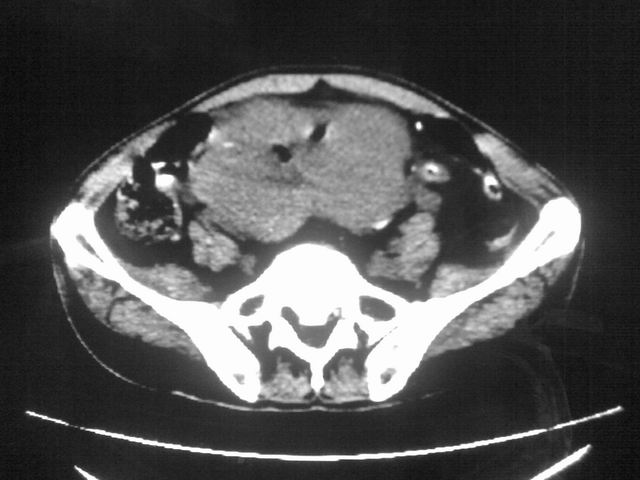

患者m 56岁,盆腔及下腹部胀痛半年,加重1月余,消瘦\中重度贫血.(附:平扫时直肠的高信号为,残留的钡剂).补一下病史:胃镜及纤维结肠镜均无明显异常.

首先是病灶的定位,平扫看很象肠管肿瘤但既然纤维结肠镜正常就可以除外结肠病变,增强成不均匀强化,位于右下腹部应该首先考虑回肠末段占位性病变,1淋巴瘤,2间质瘤,3腹膜后神经原肿瘤待除外,

膀胱后方及直肠前方见巨大混杂密度影,与前列腺相连且向膀胱内突入,精囊腺显示不清;考虑前列腺癌侵犯精囊、膀胱。

膀胱及直肠间有不规侧的软组织密度影,内密度不均匀。其内有坏死囊变,前列腺及精囊腺,膀胱后壁受浸。结合病史考虑腹膜后肉瘤可能性大。